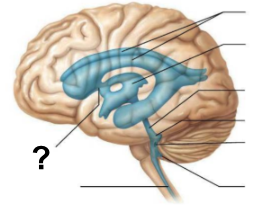

From the lateral ventricles, CSF flows through which structure, labeled “?”, to reach the third ventricle?

Interventricular foramen